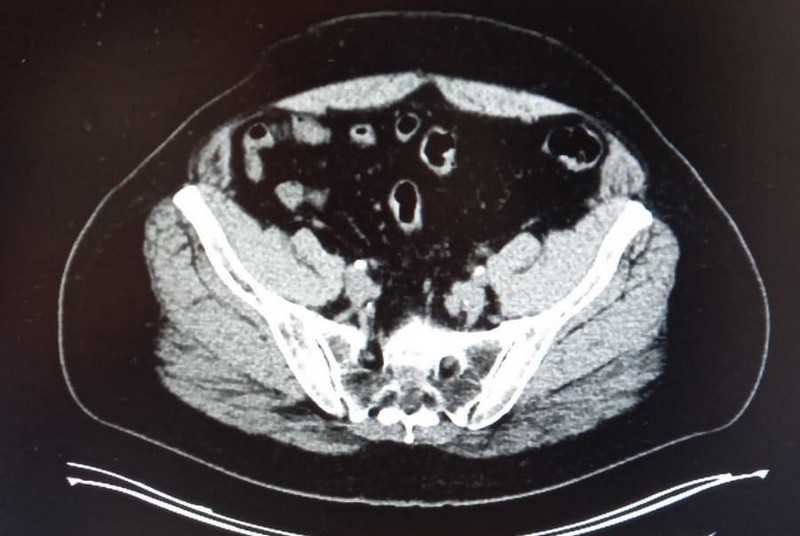

— Александр обратился к нам после того, как московские врачи диагностировали у него злокачественную опухоль легкого. Мы провели ревизию диска с результатами компьютерной томографии, который привез пациент. Кроме того, были выполнены биопсия, ПЭТ-КТ и другие исследования. Диагноз подтвердился: у Александра был обнаружен плоскоклеточный рак левого легкого 3-й стадии. Опухоль находилась в области корня легкого, прилегала к бронхам и крупным кровеносным сосудам. Ее размер составлял 4.2 см. Были поражены лимфатические узлы в центральной части грудной клетки, что указывало на местное распространение болезни. При этом проведенная нами ПЭТ-КТ не выявила отдаленных метастазов в другие органы.

— В ноябре Александр начал проходить химиоиммунотерапию. После 2 курсов лечения была выполнена КТ органов грудной клетки. Она показала, что опухоль в левом легком уменьшилась: вместо 4.2 см ее размер составлял 3.5 см, что свидетельствовало об эффективности терапии. Однако новообразование все еще прилегало к бронхам и крупным сосудам, что затрудняло его хирургическое удаление. Кроме того, на КТ сохранялись увеличенные лимфатические узлы. Поэтому пациенту было рекомендовано завершить 3-й курс лечения, после чего пройти консультацию торакального хирурга.

— Когда Александр завершил курс химиоиммунотерапии, я выполнил ему ПЭТ-КТ. Это исследование показало, что опухоль в левом легком продолжает уменьшаться: ее размеры составляли уже 1Х1.5 см. Новых очагов рака выявлено не было. Однако опухоль по-прежнему прилегала к бронхам и крупным сосудам.

— По результатам ПЭТ-КТ, проведенной после лечения, стало ясно, что расположение опухоли вблизи крупных кровеносных сосудов затруднит ее полное удаление. Ранее мы провели молекулярно-генетическое тестирование опухоли и выявили мутацию гена KRAS G12/13. Такая мутация часто встречается при раке легкого, особенно у пациентов с историей курения. Клинические исследования показали, что при наличии такой мутации опухоль обычно хорошо реагирует на иммунную терапию.